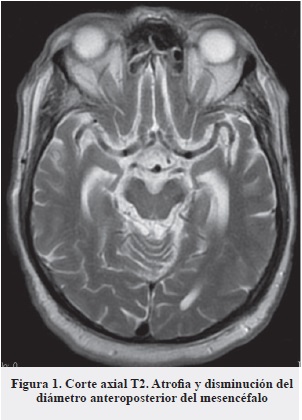

Al ingreso se registraron los siguienes paraclínicos: glucemia basal 166 mg/dL; cloro: 92; potasio: 4,84; sodio: 123, creatinina: 0,74; BUN: 11,7; PT: 10,5; PTT: 25,8; INR: 0,97. Hemograma: leucocitos: 11,6; neutrófilos: 9,6; linfocitos: 1,36; Hgb: 8,51; VCM: 90; Htcto: 24,5; Plaq: 292.000. Posterior a valoración inicial se obtuvieron paraclínicos de vitamina B12: 189; VIH: no reactivo; VDRL: no reactivo; ácido fólico: 14,2; TSH: 1,12; Hgb glicosilada: 6,6. Desde el punto de vista neurológico, dada la presencia de caídas frecuentes, parkinsonismo sin respuesta a levodopa y parálisis de la supraversión de la mirada, se complementó estudio con una resonancia magnética de cerebro (Figura 1) en la que se evidenciaron hallazgos sugestivos de parálisis supranuclear progresiva.

En nuestro caso la realización de la resonancia de cerebro constituyó una herramienta muy útil que, además de argumentar la sospecha clínica inicial, sirvió para descartar otras lesiones estructurales asociadas a caídas frecuentes (hematomas, hidrocefalia a presión normal, etc. ). Los hallazgos característicos de esta enfermedad son, principalmente, la atrofia del tegmento del mesencéfalo (Figura 2) en proyección sagital (signo del colibrí o del pingüino) (Figura 3) (16, 17), la alteración del diámetro anteroposterior y la atrofia generalizada del mesencéfalo (Figura 4) (18).